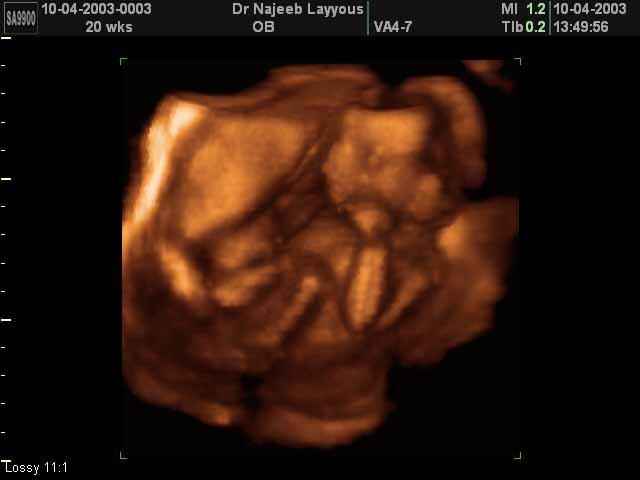

- Fetal Parts Ultrasound Scan Photos

3D Second Trimester Ultrasound Scan Photos-second part of pregnancy | Dr N Layyous